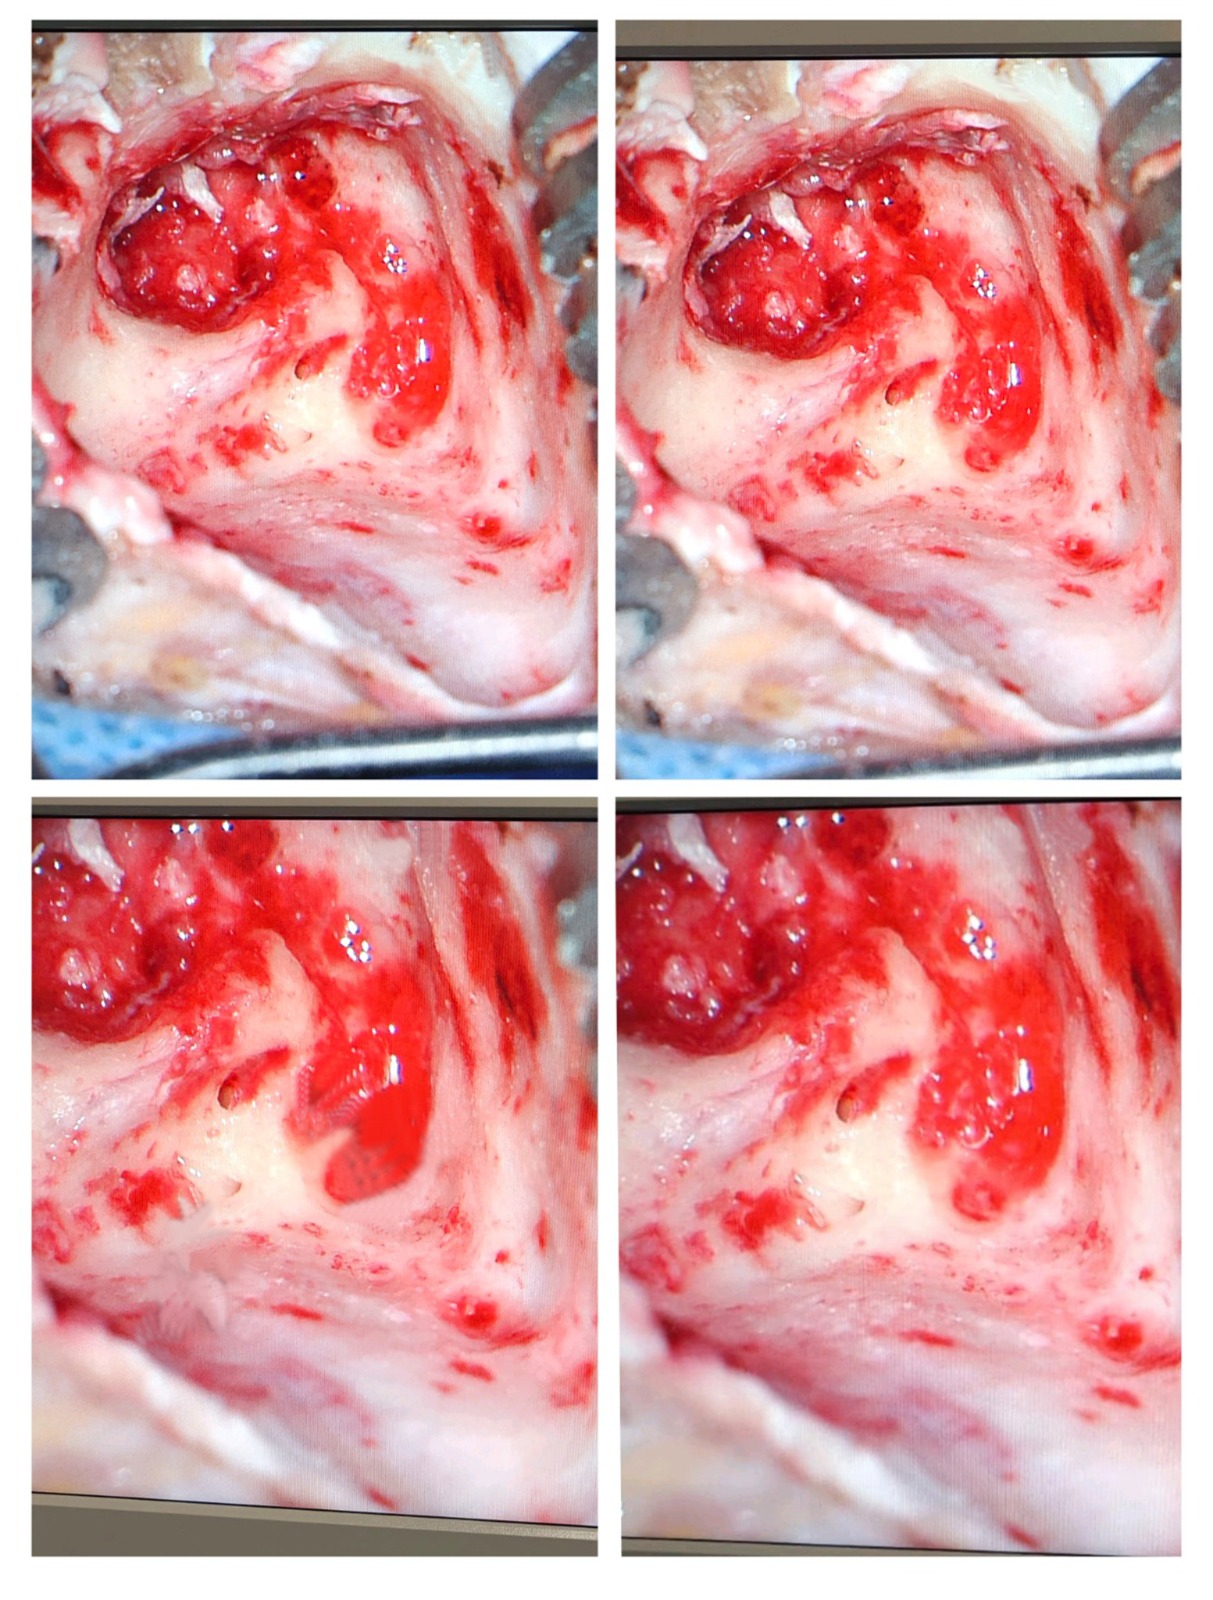

- Cholesteatoma (abnormal skin growth inside the ear)

3. Ossiculoplasty (Middle Ear Bone Reconstruction)

Ossiculoplasty reconstructs or replaces damaged ossicles (hearing bones: malleus, incus, stapes).

Why It’s Needed

- Injury

- Infection

- Cholesteatoma

- Chronic middle ear disease